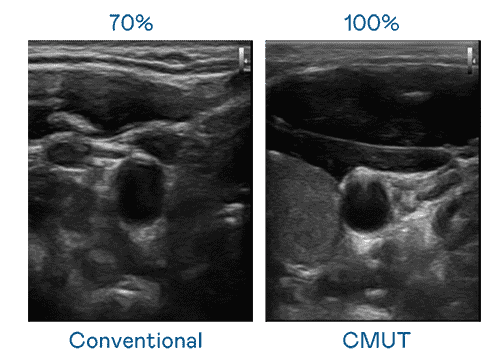

CMUT 技术是一种用电容式微机电元件来产生超音波讯号的技术。。。与传统 PZT 压电式技术相比,,,,CMUT 频宽增加 30%,,,,更宽频的超音波讯号让影像解析度大幅提升,,,是实现高影像品质医疗超音波扫描、、、、促进精准医疗发展的关键技术。。。。

大频宽带来超清晰影像

超音波影像的解析度高低,,,,首先取决于探头能发出的讯号频宽。。。万利 CMUT 可提供高清晰的超音波讯号,,,提供高频宽、、高灵敏度、、、影像纹理细节更高的超音波影像,,,协助医护人员缩短影像判读时间及利用精准的医疗影像进行诊断。。。。